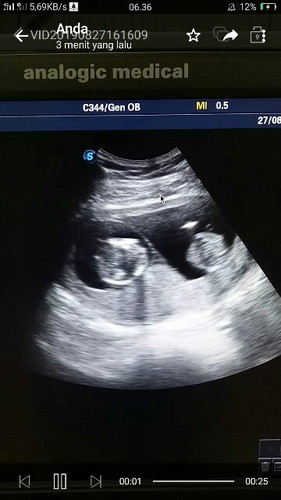

Bundaa, mau tanya nih.. Apa benar yaaa kalo hamil anak kembar nggak boleh berhubungan sex sampe lahir yaa bun.. Mohon pencerahanya bunda..